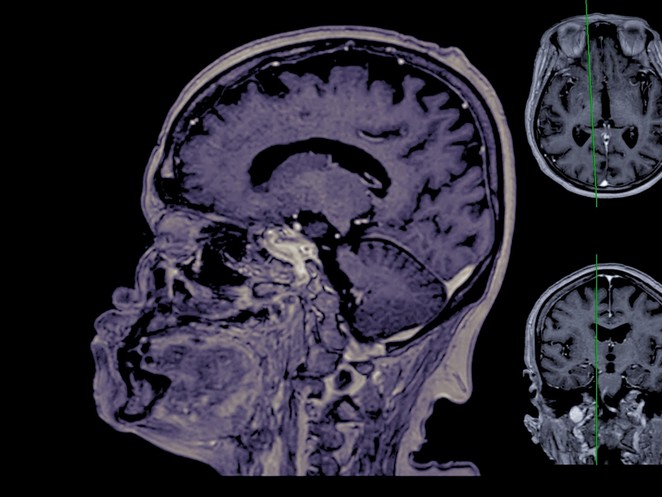

Medizin

Darum gibt's neue Hoffnung im Kampf gegen Alzheimer

Fortschritte bei Vorhersage des kognitiven Zerfalls bei Alzheimer